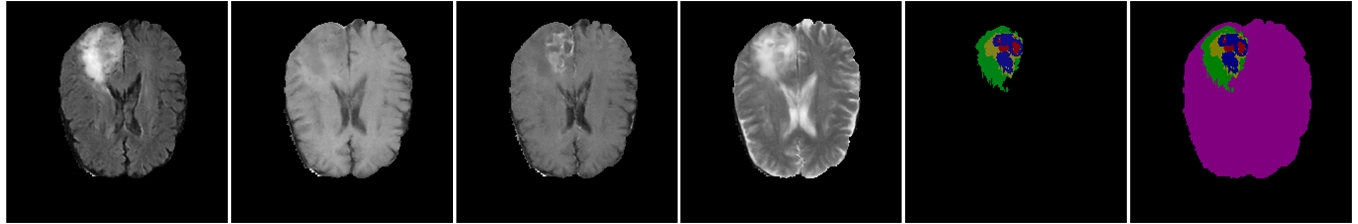

Refer to caption

Figure 3: Comparison of traditional augmentation and our proposed method. First row: Original image. Second row: Augmented image using elastic deformation. Third row: synthetic image generated by our approach. Left to right: FLAIR, T1, T1c, T2 and semantic label map

The traditional augmentation approach for object segmentation often uses different combinations of affine transformations, such as shifting, rotation, and zoom, to leverage the knowledge of invariances in a task. However, such knowledge implied by these affine transformations is limited. For example, the shape, location and appearance of a complete tumor in a multi-modal MR image can vary significantly in the testing data, but the augmented image produced by the typical data augmentation fails to β€œsimulate” such changes. Although some interpolation-based techniques such as elastic deformation can cause a slight variation in the shape of the augmented image, it may bring about damage and noise to the training data, as shown in fig. 3, if the deformation field varies a lot.

Instead, we propose applying the elastic deformation to the label map. After that, we create a set of semantic labels from the deformed label maps. Specifically, we label 111 to 555 for necrosis, edema, non-enhancing tumor, enhancing tumor, non-tumor brain regions and 00 for everything else in the semantic labels. We use the semantic labels instead of the label maps as input for our proposed CB-GANs. By providing the information of the contour of the brain to the generator, it further diversifies the synthetic brain MR image with different shapes and prevents model collapse, i.e., prevents the model from generating a set of realistic MR images with the identical shape and context of the brain. Figure 2 and 3 show the example of the synthetic image generated by CB-GANs with corresponding semantic label map.